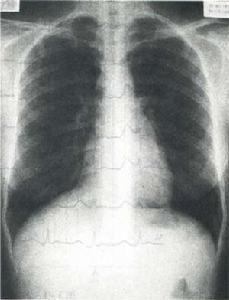

肋骨人肋骨12對,左右對稱,後端與 胸椎相關節,前端僅第1-7肋借軟骨與 胸骨相連線,稱為真肋;第8-12肋稱為假肋,其中第8-10肋借 肋軟骨與上一肋的軟骨相連,形成 肋弓,第11、12肋前端游離,又稱浮肋。

肋骨第1肋骨短小而彎曲,頭和頸稍低於體,肋體扁,可分為上、下兩面和內、外兩緣。上面內緣處有前 斜角肌附著形成的前斜角肌結節,結節的前、後方各有淺溝,是 鎖骨下靜脈和 鎖骨下動脈的壓跡。下面無肋溝,前端借 肋軟骨直接與 胸骨相結合。第2肋比第1肋稍長,更近似於一般肋骨。第11、12肋無肋結節、肋頸及肋角,體直而短,末端鈍圓。肋軟骨終身不骨化。